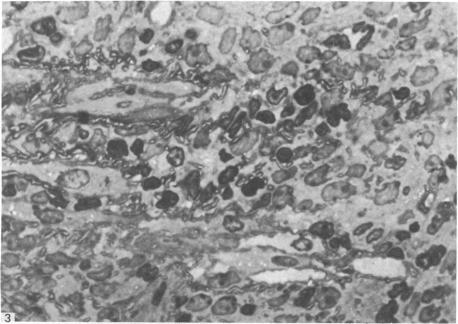

The role of oestrogen in the recruitment of GMG cell precursors to the uterus has been investigated in radiation-induced chimeric mice reconstituted with rat bone marrow and maintained on a hormone regime simulating pseudopregnancy. The presence of rat GMG cells in the deciduomata in mice irradiated after oestrogen priming suggests that oestrogen priming is not an essential factor in recruiting GMG cell precursors. However, the results have led to the suggestion that in the normal, cycling mouse oestrogen may have a role in attracting GMG cell precursors to the uterus and preparing them for differentiation.

雌激素在将GMG细胞前体募集至子宫中的作用,已在经大鼠骨髓重建并维持于模拟假孕激素方案下的辐射诱导嵌合小鼠中进行了研究。在雌激素预处理后接受照射的小鼠蜕膜中存在大鼠GMG细胞,这表明雌激素预处理并非募集GMG细胞前体的必要因素。然而,这些结果提示,在正常的周期性小鼠中,雌激素可能在吸引GMG细胞前体至子宫并使其为分化做好准备方面发挥作用。